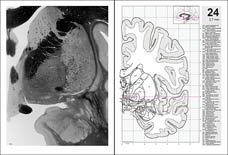

Atlas of the HUMAN BRAIN

Example pages from the printed book:

atlases. The new edition is completely redesigned, with additional magnetic

resonance images, line drawings, and an extensively expanded section of coronal

images. The number of hemisphere sections has been doubled, and all planes of

sections are placed within the Talairach space. The

format of the atlas has been enlarged and the information reorganized on the